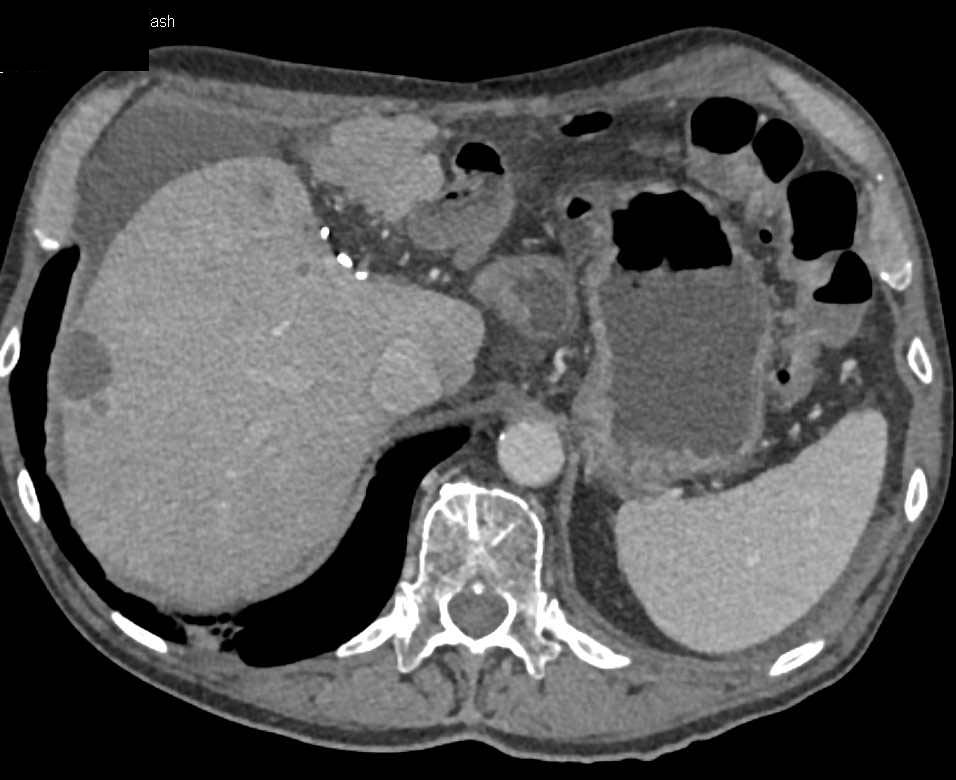

Ovarian Carcinoma